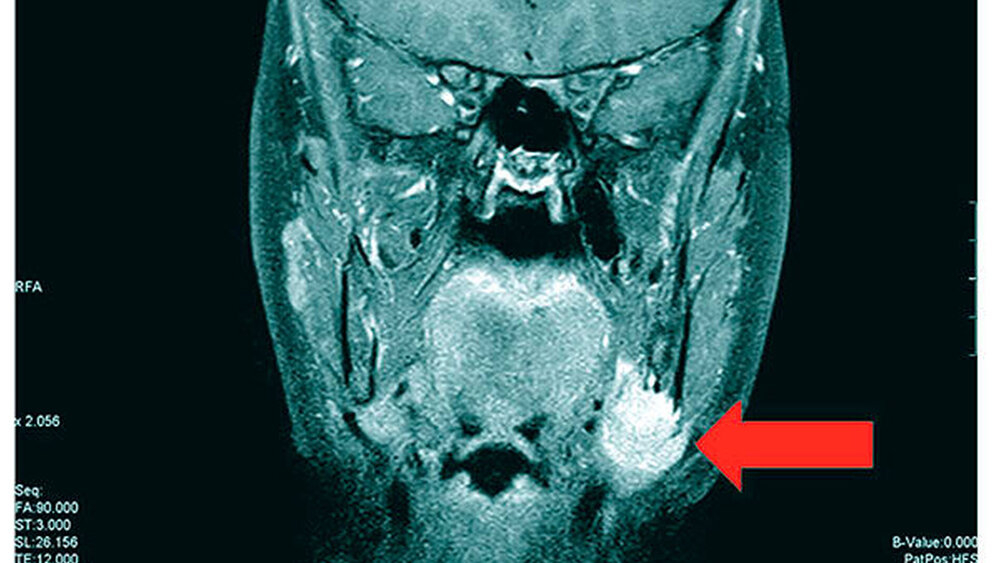

Die Magnetresonanztomografie des Neuro- und des Viszerokraniums erbrachte den Nachweis eines Areals erhöhter Kontrastmittelaufnahme im Bereich des basalen Kieferwinkelrandes links mit einer Ausdehnung von 3,1 cm x 2,3 cm. Im Bereich der behaarten Kopfhaut zeigten sich subkutan T1-hypointense, zum Teil polylobulierte Läsionen mit Verdacht auf epidermale Zysten sowie subgaleale T2-hypointense, flächig kontrastmittelaufnehmende Läsionen mit Verdacht auf Osteome (Abbildungen 3a bis 3d).